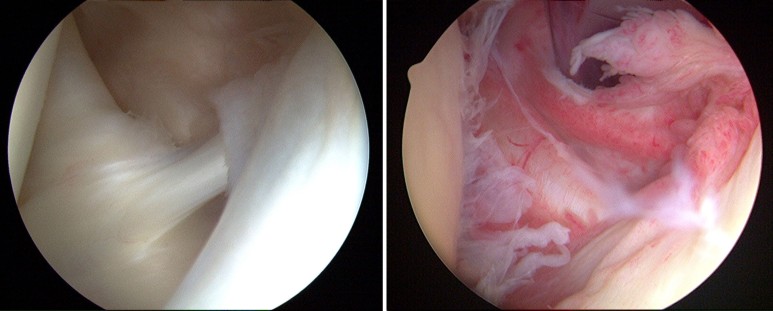

예쁜 관절(왼쪽), 관절내염증(오른쪽)이 여러가지 이유로 염증이 생기면 관절주머니가 두꺼워지고 딱딱해지는 문제가 발생합니다. 관절 내에 있는 윤활액도 부족하여 어깨 관절을 움직이기 어렵고 염증에 의해 움직일 때마다 통증이 유발됩니다.

- 관절경 : 관절 주머니의 딱딱한 부분을 잘라냅니다.0~8주●목표-관절가동범위증가-통증감소●물리치료-담당처방에 의한 초음파-담당처방에 의한 충격파-재활운동전 온찜질, 후냉찜질●관절가동범위증가운동 모든 운동전…functional-therapist.tistory.com상의 링크에서 나오는 운동을 시기에 맞게 진행해 주세요.